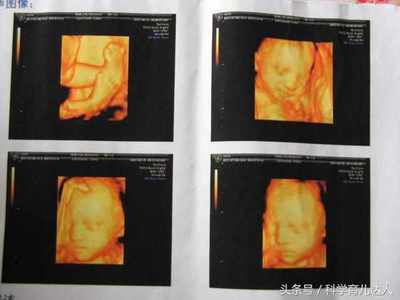

问医生。妊娠在四维彩超中起什么作用?随着科技的发展,孕期四维彩超已经成为一个大家比较熟悉的检查项目,也是孕期的常规检查项目之一。但是,四维彩超检查有什么优势呢?同时,孕妈妈为什么要做四维彩超检查?孕期四维超声可以判断胎儿的所有外观结构。四维超声最大的作用就是看胎儿的外观结构是否健全。它就像一双x光眼,能看到肚子里的宝宝。

四维彩超不仅能让准爸妈提前“见到”自己未出生的宝宝,还具有对胎儿进行各种检查的主要功能,以便尽早发现胎儿生长中的问题,如唇裂、脊柱裂等。此外,四维彩色多普勒超声的图像显示比传统的彩色多普勒超声和b超更清晰准确。因此,为了孕妇和胎儿的健康,选择四维彩超是非常必要的。1.孕妇在任何孕周都可以做四维彩超。但需要注意的是,妊娠早期(孕12周前)是否可以做四维b超是有争议的。

一般来说,妊娠2428周是四维彩超的最佳时间,因为胎儿24周左右是大脑快速发育的时期,这期间胎儿结构已经形成,胎儿大小和羊水适中,在子宫内的活动空间较大,胎儿骨回声的影响相对较小,图像相对清晰。四维超声在三维超声的基础上具有实时动态效果。准爸爸和准妈妈可以通过屏幕见证宝宝在妈妈肚子里的运动、呼吸、吞咽、打哈欠、吐舌头等生理活动,非常直观。

1.为了给宝宝全身拍照:这个时候可以选择在孕早期做四维彩超。此时宝宝还小,可以通过仪器拍下宝宝的全身。值得提醒的是,12月不建议做四维彩超。这个孕期做四维彩超是有争议的。2.为了检查宝宝的外部缺陷:此时可以选择在孕中期或孕晚期做四维彩超。此时宝宝的身体已经发育到一定程度,不可能给宝宝全身拍照,但是可以观察宝宝某个部位的形态。